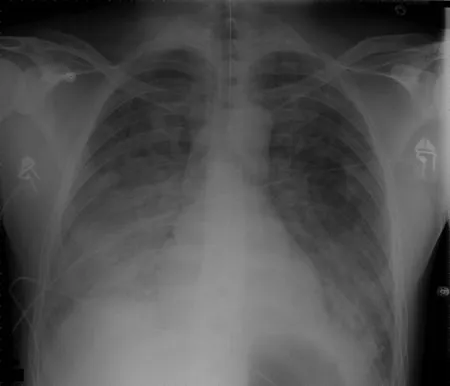

| Aortic dissection | Widened mediastinum on CXR | 60% | 85% |